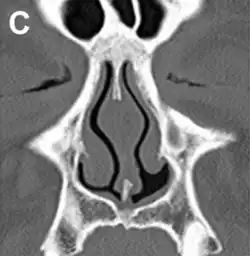

Diagnosis

No consensus criteria exist for the diagnosis of ENS and many ENTs will wait a year before diagnosing in hopes the patient accepts the new airflow; it is typically diagnosed by ruling out other conditions, with ENS remaining the likely diagnosis if the signs and symptoms are present.[3][7][13] A "cotton test" has been proposed, in which moist cotton is held where a turbinate should be or in various locations in the nasal passages, to see if it provides relief and an airflow pattern that allows for natural breathing; while this has not been validated nor is it widely accepted, it may be useful to identify which people may benefit from surgery.[3][7][13]

As of 2015, protocols for using rhinomanometry to diagnose ENS and measure response to surgery were under development,[7][13] as was a standardized clinical instrument (a well defined and validated questionnaire) to obtain more useful reporting of symptoms.[13]